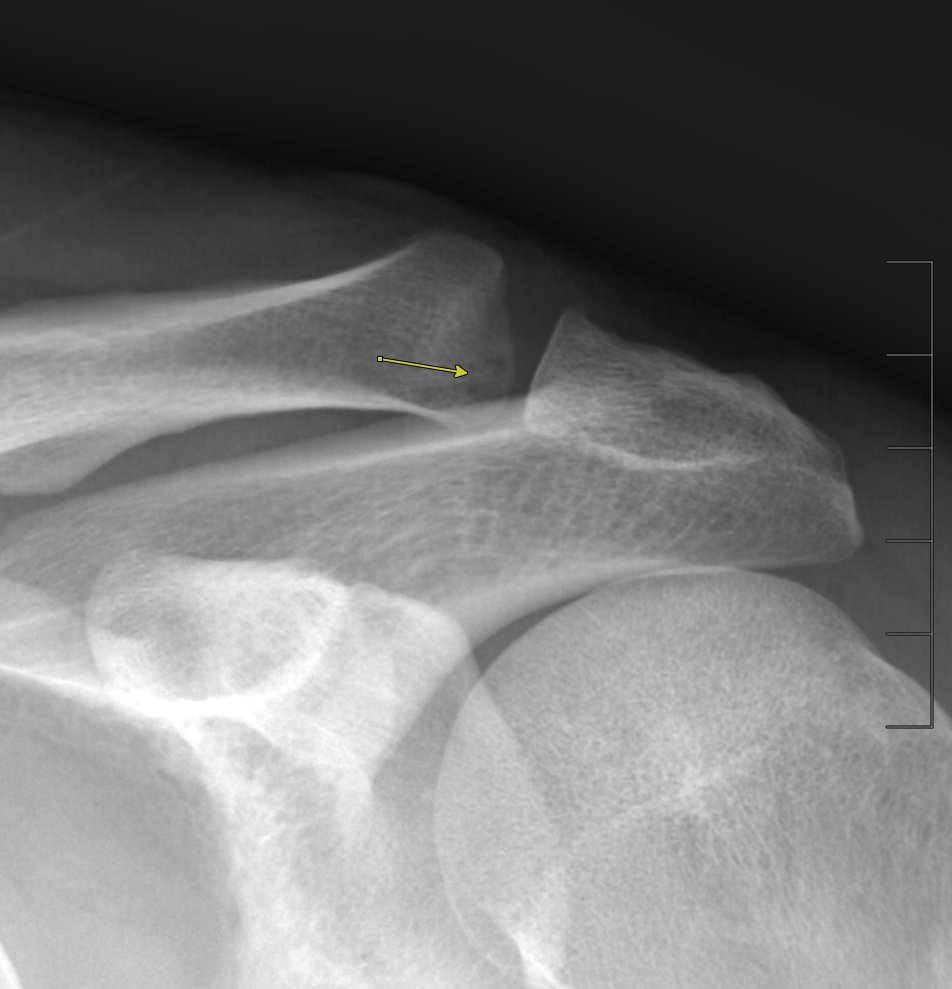

From www.semanticscholar.org

Figure 1 from Stress fracture of the clavicle in a patient with no Stress Fracture Clavicle Symptoms a stress fracture occurs when the adaptive ability of the bone is unbalanced. learn about the common causes, symptoms and treatment of a clavicle fracture, also known as a broken collar bone. Find out how to manage your pain,. Learn how to prevent and. Pain that starts and gets worse during physical activity. the most common symptoms. Stress Fracture Clavicle Symptoms.